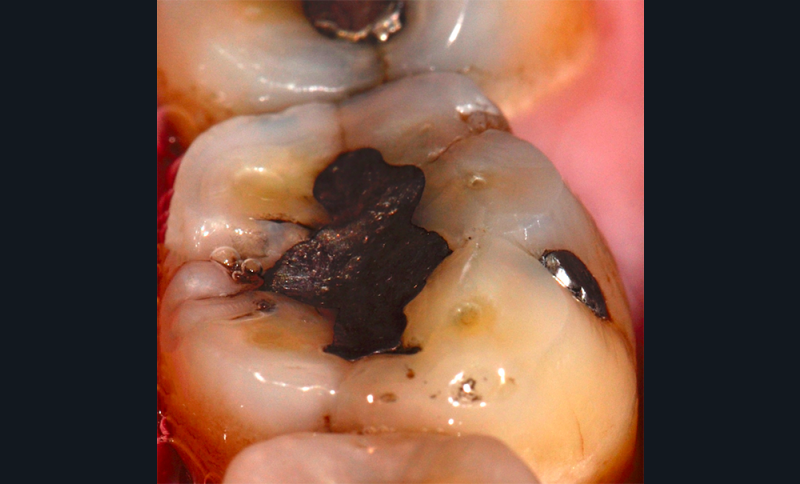

Aspect clinique et radiographique des lésions d’abrasion

Cliniquement, les lésions d’abrasion sont caractérisées par des facettes lisses, une absence de convexité et des bords à angles vifs. La flexibilité du ligament alvéolo-dentaire va entrainer un frottement au niveau des points de contact, qui peuvent se transformer en surfaces de contact (fig. 2c-d, 3 et 4b-c).

Radiographiquement, on observe une perte des cuspides et un aspect plan des faces occlusales (fig. 2a-b et 4a).